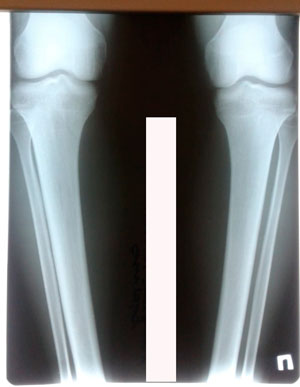

Исходник - 27 лет.

Дата операции - 07.08.2020

Дата снятия аппаратов - 10.12.2020